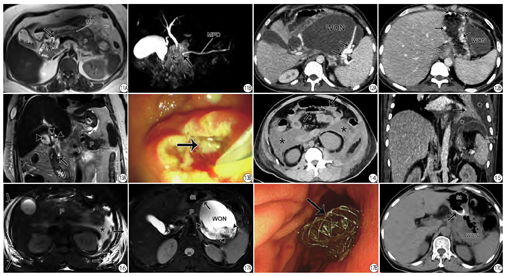

肝脏大部分由门静脉系统供血,当发生AP时,很多炎性因子和游离脂肪酸可短时间内汇集于肝脏,故可见脂肪肝的CT/MRI表现。笔者前期研究发现66%的AP患者在MR上可检出脂肪肝征象;且通过IP/OP图像定量的肝脏信号差异值与MRSI呈正相关;随着血浆甘油三酯水平的降低,脂肪肝表现可逐步恢复正常[11]。胆系结石尤其是胆总管结石的诊断对临床治疗方式的选择有提示作用[12],故针对胆石性胰腺炎(图13)需着重描述。此外,AP炎症渗液对胃肠道影响也较大,常致肠管郁张、不全肠梗阻(图14)[13],这与患者腹胀、腹内压增高相关。

就胸部CT而言,AP多合并胸腔积液及压迫性肺不张的表现(图15),这可能与患者出现呼吸功能不全有关联;AP还可引起腹壁皮下水肿、积液改变(图16)。研究发现53.8%的AP患者在MR上出现胁腹壁水肿;且腹壁水肿评分与MRSI评分呈正相关,即腹壁水肿程度能间接反映AP的严重性[8]。